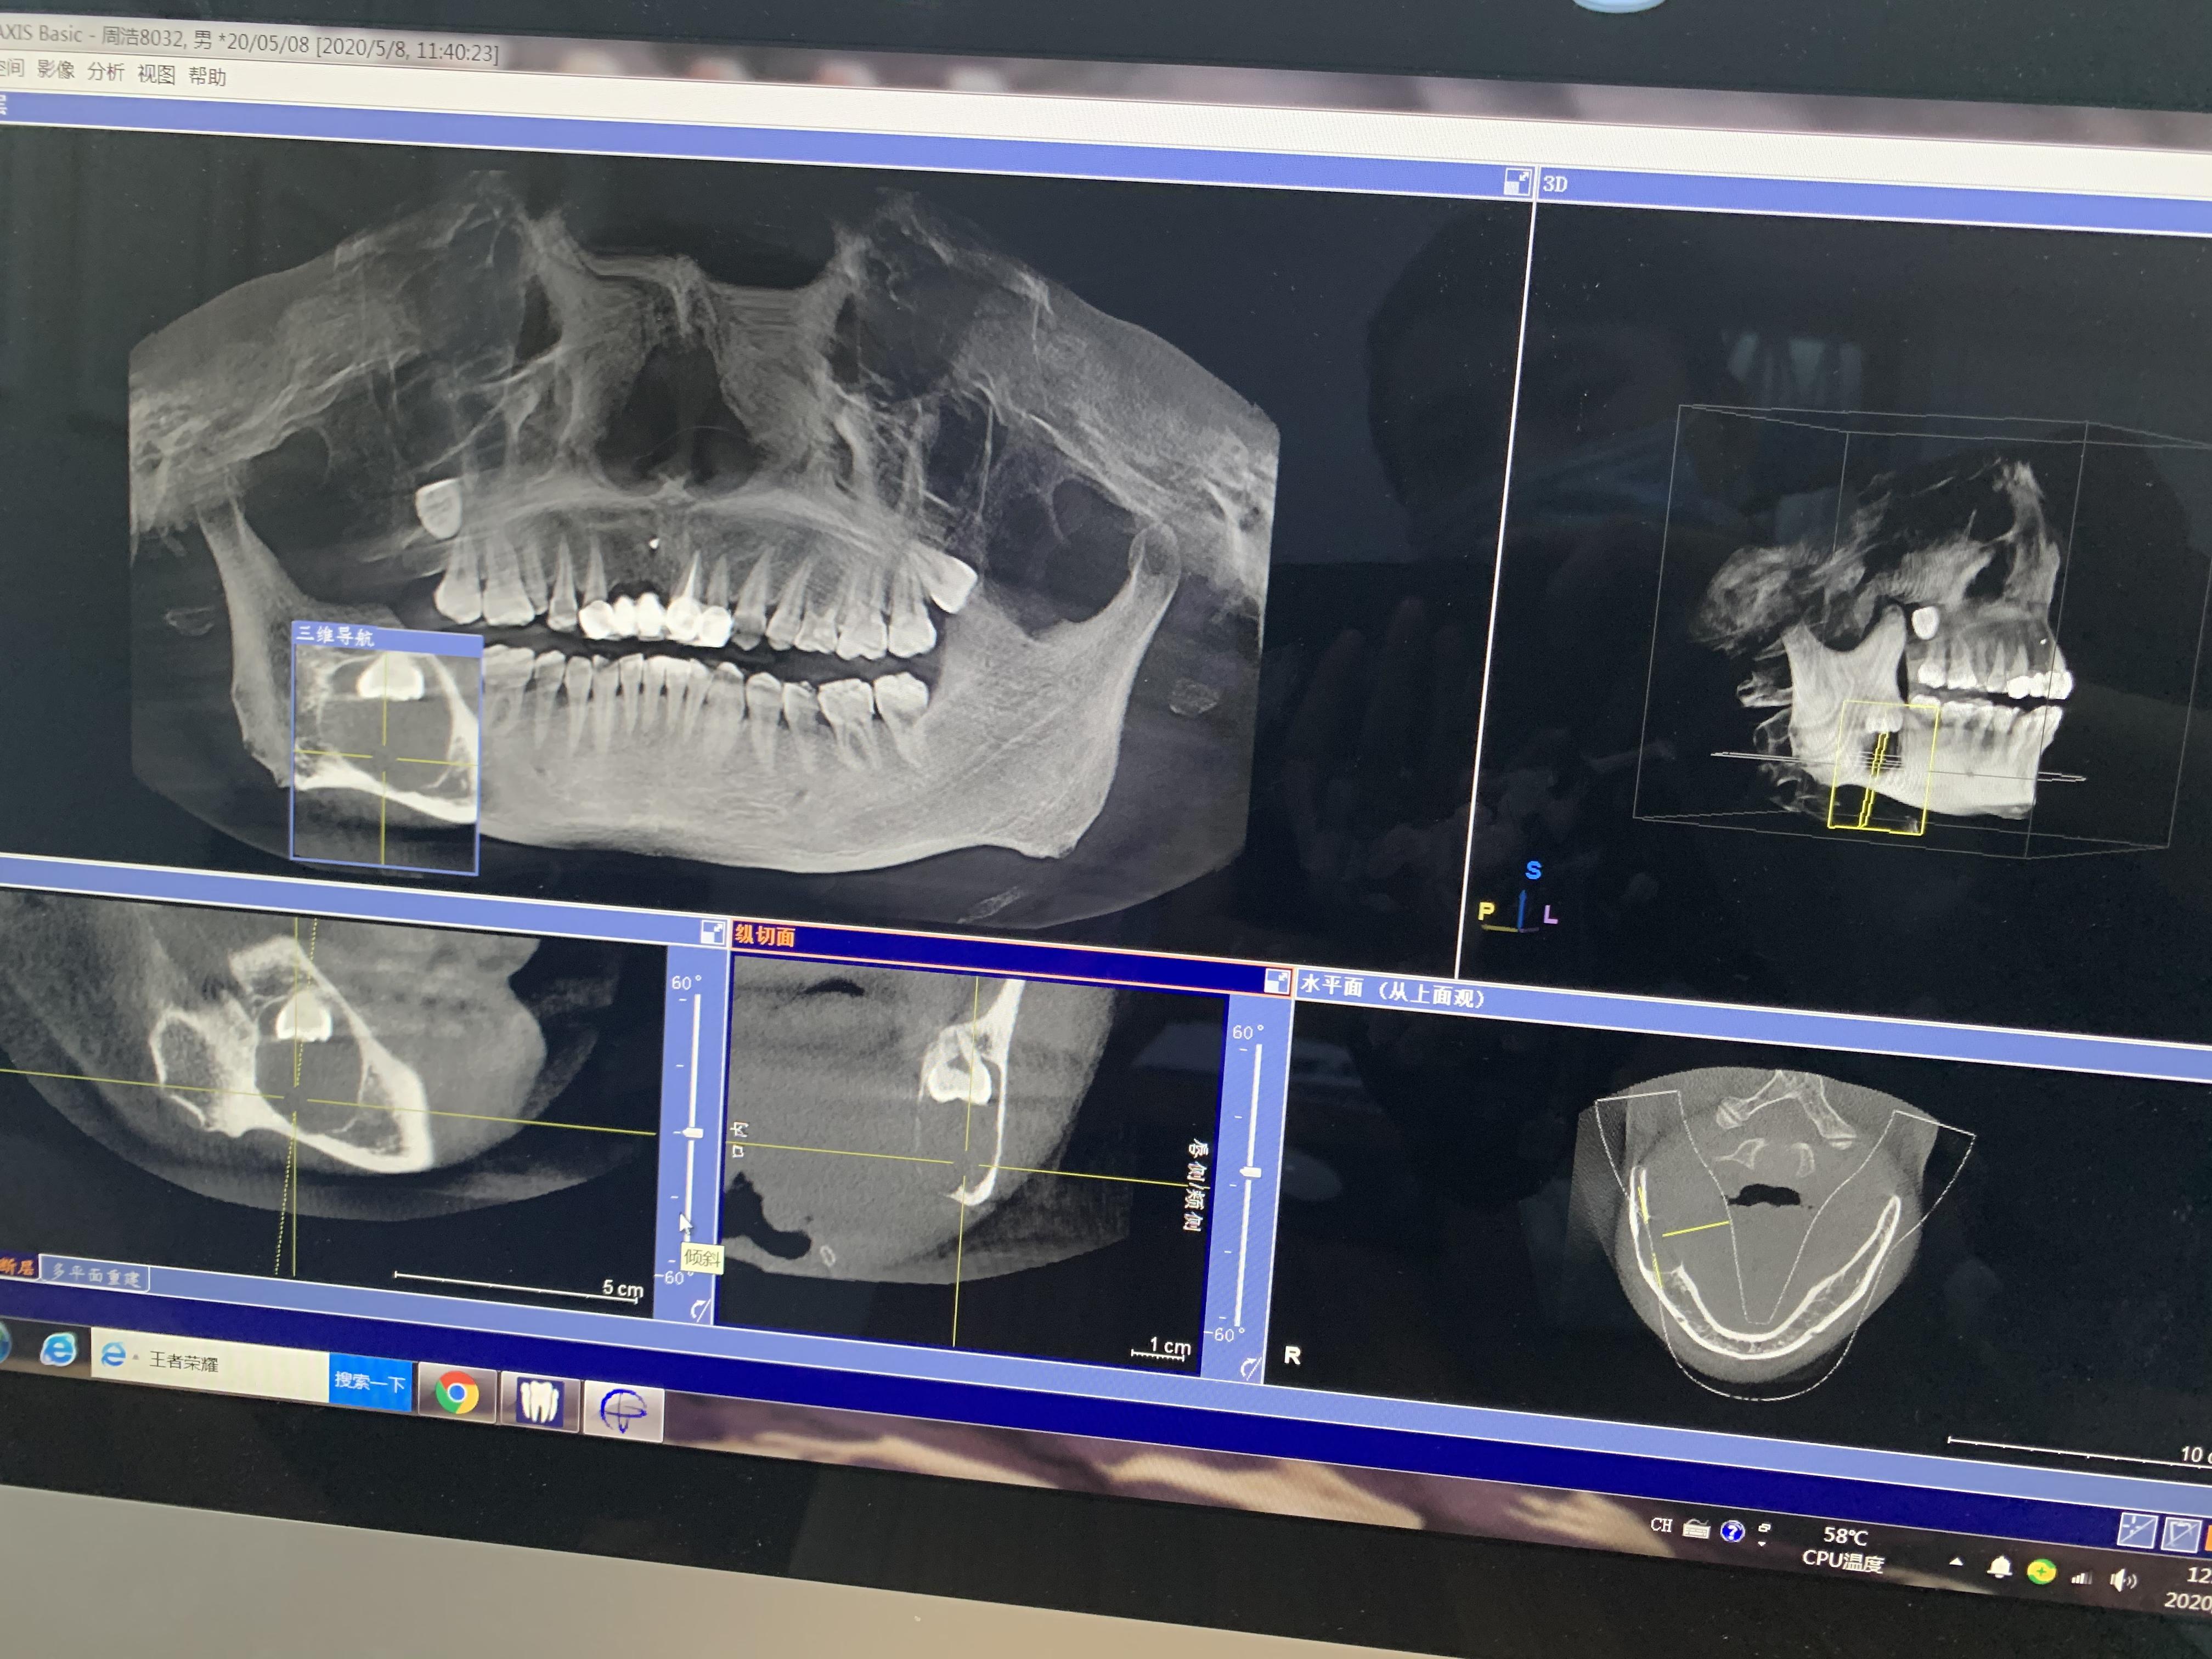

方框內(nèi)圓形的就是囊腫,從邊緣看,骨頭已經(jīng)很薄了

右下頜囊腫,倒阻生牙

下午1點(diǎn)半,片子拍好拿到了,王醫(yī)生看過(guò)后告訴我:

1.根據(jù)片子來(lái)看,囊腫確實(shí)挺大,神經(jīng)已經(jīng)被壓迫到一邊了,做完手術(shù)后右下巴和嘴唇會(huì)出現(xiàn)麻木的情況,當(dāng)然,這種情況后面也會(huì)慢慢恢復(fù),但每個(gè)人的恢復(fù)情況不一樣,所以不敢說(shuō)多久可以恢復(fù);

2.根據(jù)片子來(lái)看,可以不做開窗,開窗很多時(shí)候也是為了保護(hù)囊腫邊上的牙齒不用做拔除,但你囊腫位置不影響周圍牙齒,所以可以在手術(shù)中拔出阻生牙和囊腫刮治;